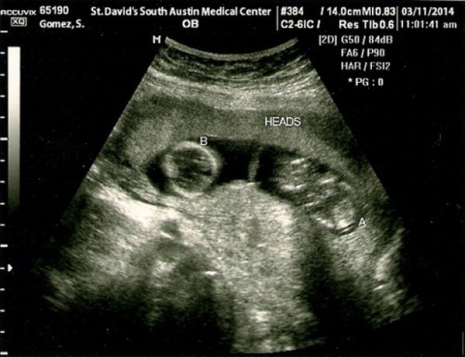

Selena Gomez és Justin Bieber pas de deux-je nagy érdeklődést váltott ki a rajongók körében, így nem meglepő, hogy az internet valósággal felrobbant, amikor napvilágot látott egy szonogrammfotó egy iker magzatpárról, amelyet egy S. Gomez nevű páciens részére készítettek 2014. március 11-én a St. David's South Austin Medical Center nőgyógyászati osztályán.

Viszont azok a rajongók, akik Jelena-babákban reménykedtek, valószínűleg nagyon csalódottak lesznek, mert időközben kiderült, hogy Selena csak egy kamuhír áldozatául esett. Az ultrahangfelvétel nem is lehet az övé, hiszen a kérdéses napon, március 11-én New Yorkban tartózkodott, ráadásul egy teljesen megegyező, 2009-es felvételt találtak egy kismama-blogon is, ami alátámasztja a gyanút, hogy egyszerűen meghamisították azt.